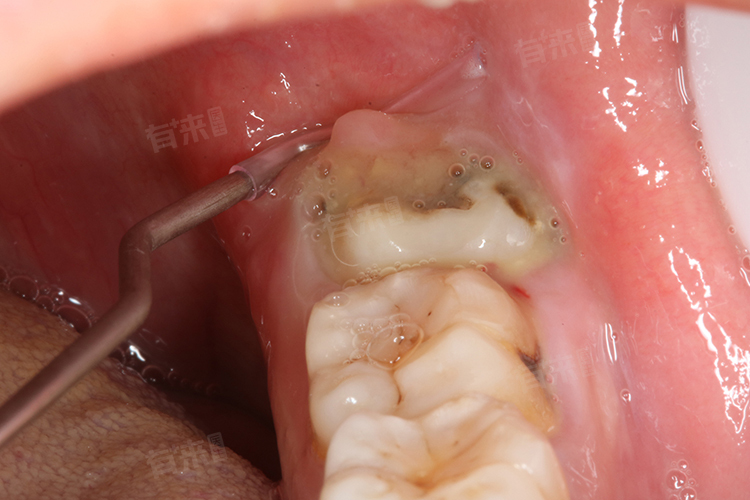

- 然而,并非所有患者都适合一次性拔除多颗智齿。医生会综合考虑多种因素,包括但不限于患者的整体健康状况、智齿的位置与生长方向、是否存在感染或炎症等。如果患者的智齿位置较为复杂(例如水平阻生),或者存在较大的手术风险,则可能建议分次进行拔除。此外,对于一些体质较弱或者有特殊健康问题的人群,如心脏病患者或糖尿病患者,医生可能会更倾向于采取保守策略,以降低手术风险并确保术后恢复顺利。

- 在决定是否一次性拔除两颗智齿之前,医生通常会对患者进行全面评估,包括口腔检查、X光片甚至CT扫描来了解智齿的具体情况。术前准备同样重要,这包括详细的病史询问,了解是否有药物过敏史或其他影响手术及愈合过程的条件。术中,专业的麻醉技术和细致的操作是保障安全的关键。术后护理也不容忽视,遵循医嘱正确使用抗生素和止痛药,保持口腔清洁,避免剧烈运动有助于加快恢复速度,减少并发症的发生。